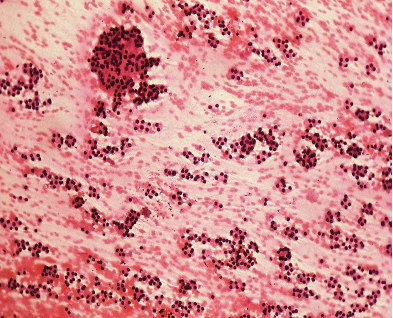

Figs 1 and 2 from a mass in the right hypochondriac region.

Fig 1 : Giemsa x 100